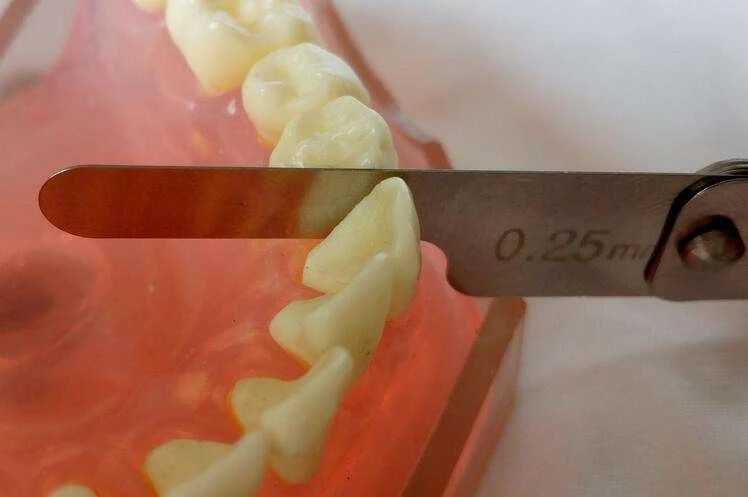

片切临床中又叫“邻面去釉”,也就是将两颗拥挤的牙齿的表层牙釉质磨掉一点,牙齿磨窄一些,制造更多空间的间隙,为矫正牙齿做准备。

事实上,人类牙齿普遍存在生理磨损,平时咀嚼食物等都会对牙齿有磨耗,这种磨损不仅发生在牙齿咬合面,还发生在牙齿的邻接点或邻接面。“邻面去釉”实际上是重现了这个自然的生理过程,只要控制在一定范围内(通常单颗邻间控制在0.2~0.5mm)是安全的。